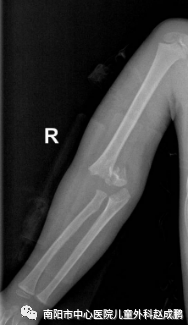

vsd引流器怎么连接创面负压封闭引流技术(VSD),让患者创面更快痊愈!_https://www.jmylbn.com_新闻资讯_第10张

vsd引流器怎么连接创面负压封闭引流技术(VSD),让患者创面更快痊愈!_https://www.jmylbn.com_新闻资讯_第11张

骨折闭合复位经皮穿针固定(不切开)术前、术后